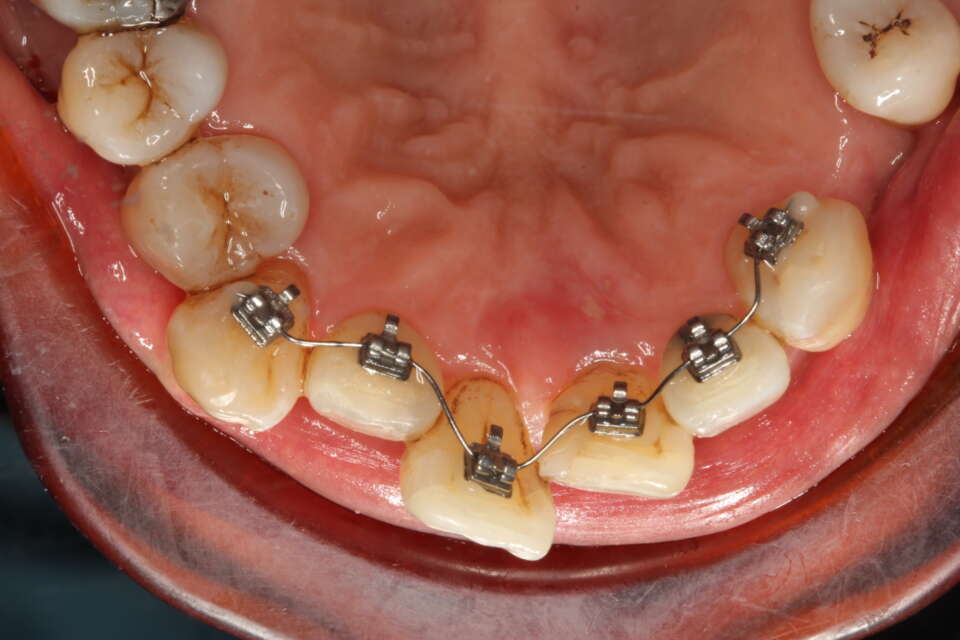

Fixed retainer

IMG 7931

We always advise having a fixed wire retainer after treatment. Retention is for life!